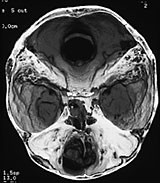

Cerebral CT med 3D-rekonstruksjon samt cerebral MR viste defekt mellom os frontale og os nasale, en stor og dyp utvidelse av fremre skallegrop og utvidelse av intrakraniale hulrom.

Pasienten ble vurdert av kraniofacialteamet og operert med kombinert ekstra- og intrakranial tilgang, som beskrevet over.